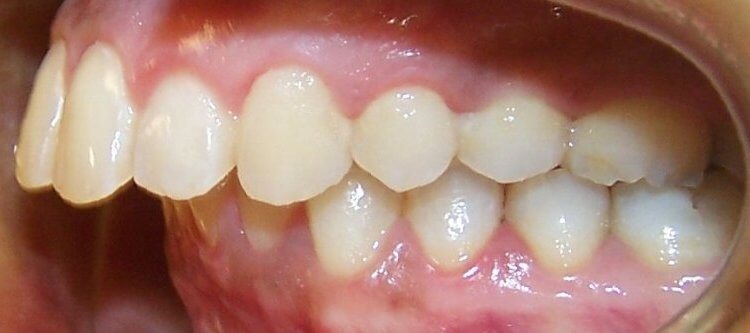

Фото 1. Дистальный прикус характеризуется более развитой верхней челюстью.

Дистальный прикус как самостоятельный тип встречается редко. В 80% случаев наблюдается сочетание 2-х патологий: прогнатического и глубокого прикусов, когда верхние резцы перекрывают нижние больше, чем на половину. Как правило, отсутствует контакт между фронтальными зубами на обоих челюстях.

Дистальный прикус — это состояние, при котором верхние зубы расположены значительно впереди нижних. Врачи отмечают, что его можно обнаружить при визуальном осмотре: если при закрытии рта верхние резцы перекрывают нижние более чем на один сантиметр, это может быть признаком проблемы. Кроме того, пациенты могут испытывать трудности с жеванием и говорить о дискомфорте в области челюсти.